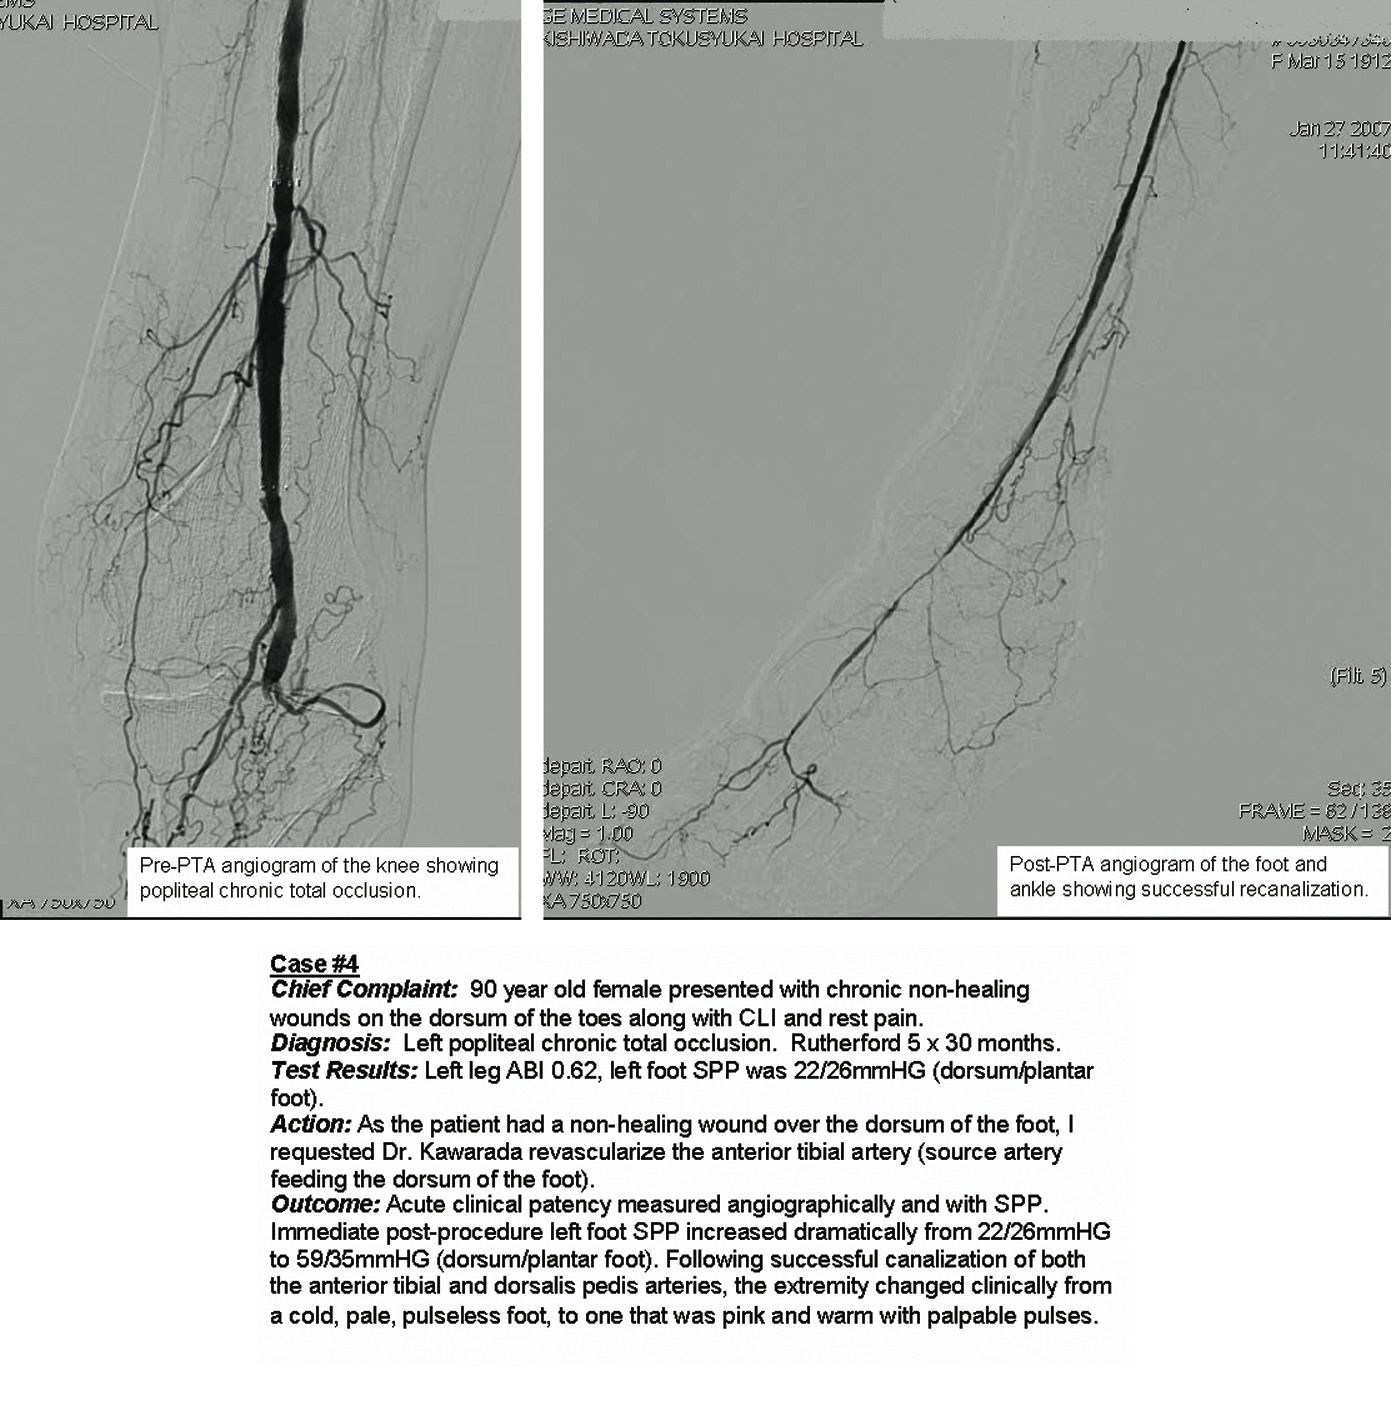

In the third case (see left photo), a diabetic patient on dialysis presented with a non-healing great toe wound with exposed bone. There was a monophasic PVR, the SPP was 41 mmHg on the plantar foot (slightly ischemic) and 21 mmHg on the dorsal foot (severely ischemic). This indicated a compromised anterior tibial artery/dorsalis pedis angiosome and a diagnosis of critical limb ischemia.

We immediately referred the patient to a vascular specialist. Following a successful angioplasty, the wound eventually closed with minor toe amputation and antibiotics.